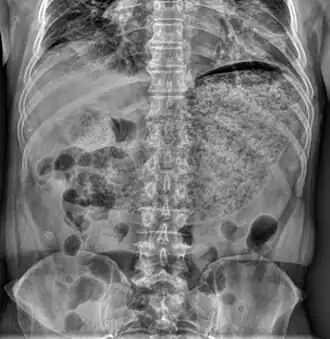

![]() Rayos X de un abdomen que demuestra una gran cantidad de materia llenando el estómago, sugiriendo una gastroparesia severa. | ||